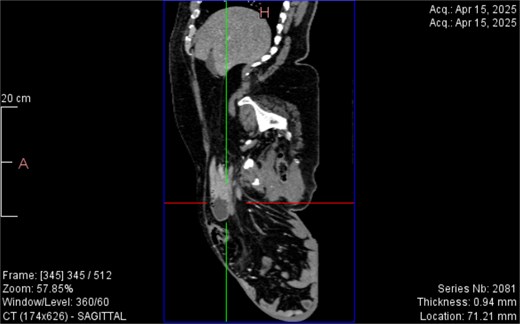

CT imaging (Figs 2–5) revealed a right inguinal hernia containing small bowel loops, ascending colon, the second and third portions of the duodenum, and the pancreatic head. The pancreatic head appeared rotated and displaced inferiorly into the hernia sac, without signs of acute pancreatitis.

Sagittal CT view inguinal hernial sac with pancreatic head and D2 and D3 segment of duodenum.